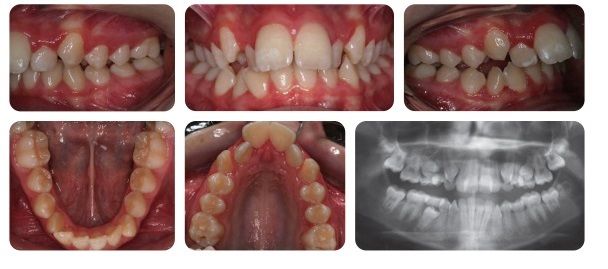

Bệnh nhân nữ 12 tuổi bị sai lệch khớp cắn hạng II tiểu loại I trên nền xương hạng II trung bình với kích thước dọc tăng, phức tạp bởi độ cắn chìa lớn (12mm), răng hàm trên và hàm dưới chen chúc. Bệnh nhân thường bị bạn bè trêu chọc về diện mạo răng-mặt.